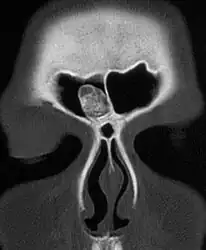

X-ray skull: Osteoma of the frontal sinus -

CT-scan skull: Osteoma of the frontal sinus -

X-ray skull: Osteoma of the frontal sinus

Medical imaging such as X-ray, CT scan and MRI show dense, clearly defined, round white tumors attached to bone.[1] They may be diagnosed when having medical imaging for another reason.[3] Osteomas of the paranasal sinuses and skull base can be diagnosed using CT-scan without intravenous contrast, allowing its size and relation to nearby important structures to be assessed.[3] A biopsy is not usually required.[3]